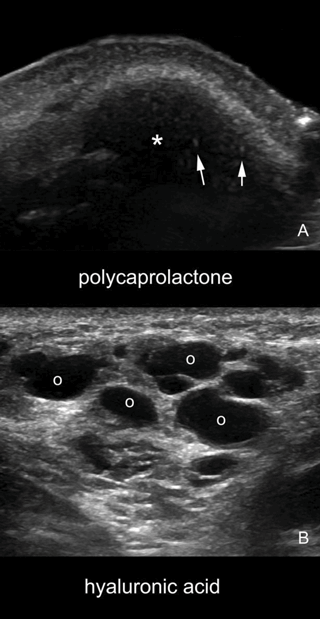

How I Do It - Approaches to lip augmentation: more than just increasing size

Having full lips is commonly associated with beauty and youthfulness. This is the reason why lip enhancement is one of the most frequently requested procedures. The complete perioral frame should be taken in to consideration to achieve a more natural...